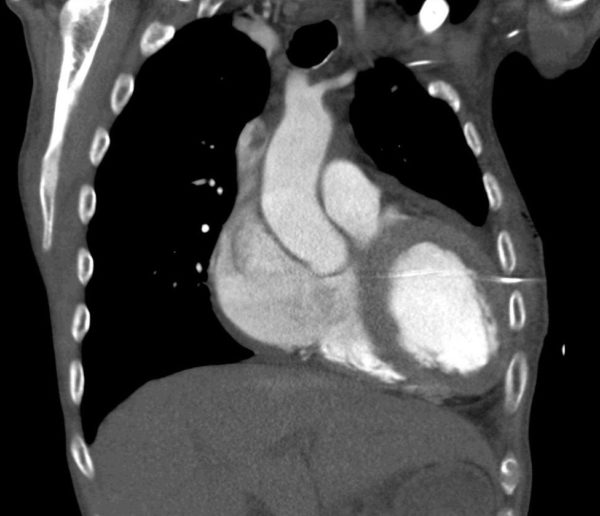

In addition to the issues of patient care, this is a sentinel event and appropriate reporting and follow-up needs to be undertaken. The CT below demonstrates how this complication arose…not everything that looks like a left pleural effusion on a plain chest X-ray is one!

In this case, the intercostal catheter is a one from a Seldinger kit. If you are going to use one of these kits, you should do an ultrasound to make sure that there really is a pleural effusion that can be safely drained.